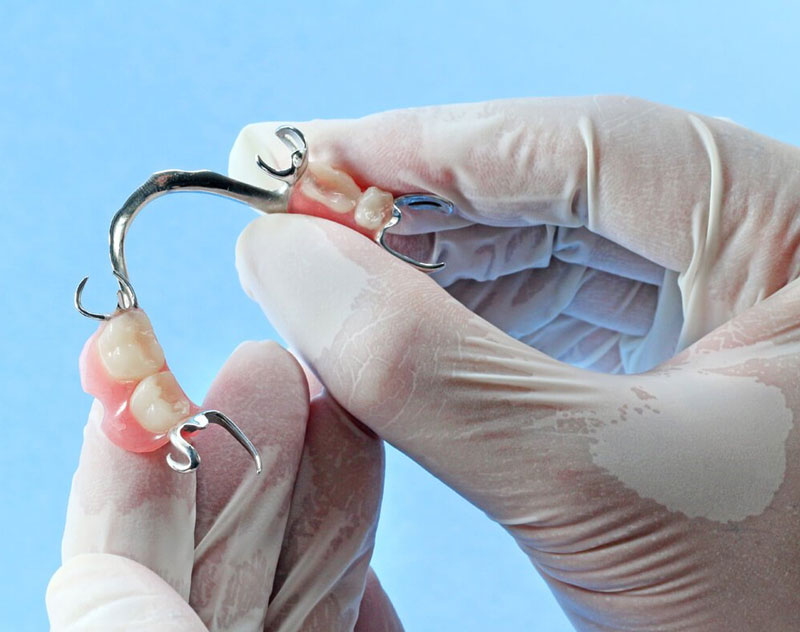

Removable implant-supported overdentures are anchored by full-size or mini dental implants, rather than resting directly on the gums like conventional dentures. This helps to replace your missing teeth by keeping the dentures in place, providing greater function and stability than conventional dentures alone.